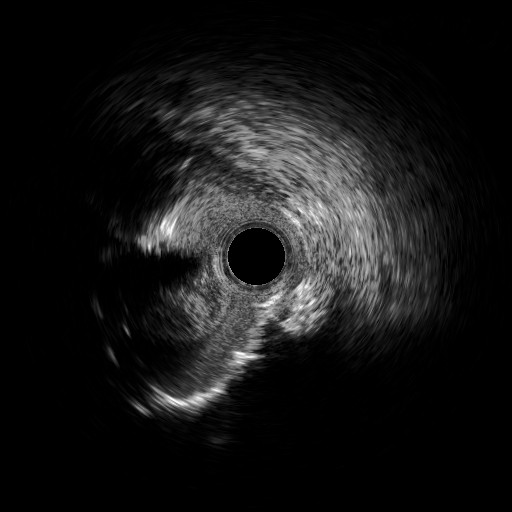

Four days later, the patient was admitted to the cardiology department because of exertional dyspnea. Because of the recent revascularization of the RCA, a new coronary angiography was performed. The angiography of the left system revealed no changes, but the RCA unveiled a nimble formation in the proximal part of the stented vessel (Figure 3, Video 3). An intravascular ultrasound was performed, which displayed the double-barrel configuration (Figures 4 and 5, Video 4) and the presence of a thrombus (Figures 6 and 7, Video 5). It was directly stented with an excellent angiographic result (Video 6). Two days postoperative, the patient was asymptomatic and discharged.